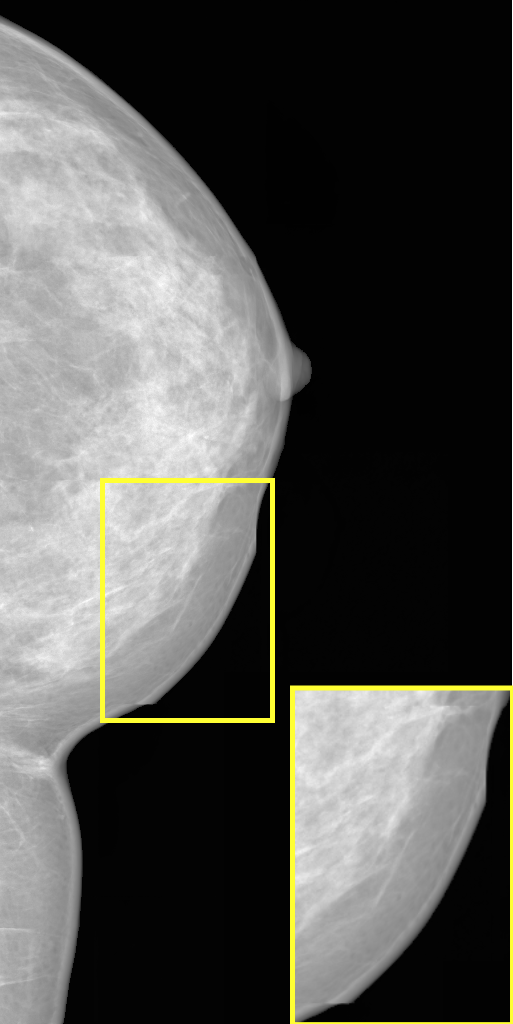

4.4 Super-Resolution

Image super-resolution (SR) refers to the task of reconstructing high-resolution (HR) images from their low-resolution (LR) counterparts [40]. In this work, SR is explored as a way to generate HR mammograms from the LR images, which can be synthesized using a standard low-resolution DDPM. Since no existing SR approaches were specifically developed for mammography, MAMBO was compared against bicubic interpolation and three general-purpose state-of-the-art SR models: AuraSR [13], DDNM [39], and LDM-SR [31].

AuraSR is used as-is, without any additional training. DDNM, in contrast, was pretrained on mammography images. Two versions of the LDM-SR model were evaluated: the original model, pretrained on the OpenImages dataset, and a second version, pretrained on mammography images, to adapt the model to the target domain. In the latter case, the original LDM-SR training procedure is followed for training both the first-stage autoencoder model (with VQ regularization) and the second-stage diffusion model (U-Net). Separate models were trained for the RSNA and VinDr datasets.

All metrics were calculated using real mammograms. Most SR models cannot upscale to arbitrary resolutions; therefore, all images were first zero-padded to a uniform size of pixels to preserve the resolution of the breast tissue. These padded images were then downscaled to pixels to serve as inputs for the SR models.

Due to the high computational demands of DDNM, LDM-SR, and MAMBO, generating full-resolution outputs at scale was not feasible. As a workaround, models were evaluated using independent image patches. Each input was first upscaled by a factor of 4 to generate a intermediate image. From this, a patch was extracted and then upscaled by a factor of 4. The final evaluation patch was obtained by center-cropping the resulting image.

Quantitative results presented in Tab. 4 and Tab. 5 show performance on patches extracted from images upscaled by and for the RSNA and VinDr datasets, respectively. Metrics were computed by comparing 2,540 output patches from each model against their corresponding original patches at the same spatial location. Visual comparisons of output patches for both datasets are shown in Fig. 4.

MAMBO outperforms all other methods on the RSNA dataset at the scale, achieving the best FID (21.82) and LPIPS (0.31), and showing notably better performance than the second-best, LDM-SR (Mammo), which scores 144.65 and 0.45, respectively. On the same scale for the VinDr, MAMBO delivers the best LPIPS and the second-best FID. At , AuraSR slightly outperforms MAMBO and LDM-SR (Mammo), but its performance degrades significantly at higher scales. Overall, MAMBO demonstrates the strongest performance, particularly at the native resolution used in digital mammography, delivering superior perceptual quality and fidelity.